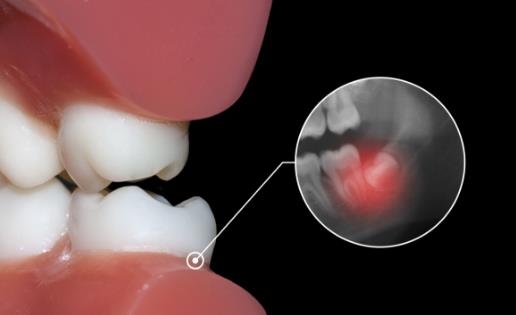

另外,由于口腔空间受限,多数人的智齿会长歪、长斜,这些“不良智齿”会有可能侵犯它的“邻居”,引起牙痛现象;如果智齿过度生长,则会导致咬合时咬到腮,引起口腔炎症;如果智齿萌发不足,则易成为阻生齿,导致牙冠周出现细菌感染,诱发炎症,出现红肿、口臭现象,如果感染广泛扩散,还可能会引起气道水肿,导致呼吸困难,危及生命!因此,以上给人体口腔带来任何不适的智齿,都应该及时拔掉,以绝后患。

通常情况下,正常生长的智齿应尽量保留,不可随意拔除。尤其是已经生长多年的智齿。只有出现非正常生长的各种临床症状,才有拔除的必要!拔除智齿之前一定要拍摄牙片,确定智齿生长是否异常。发炎的智齿也不是非拔不可。只要炎症消失,不再复发,可以不拔。